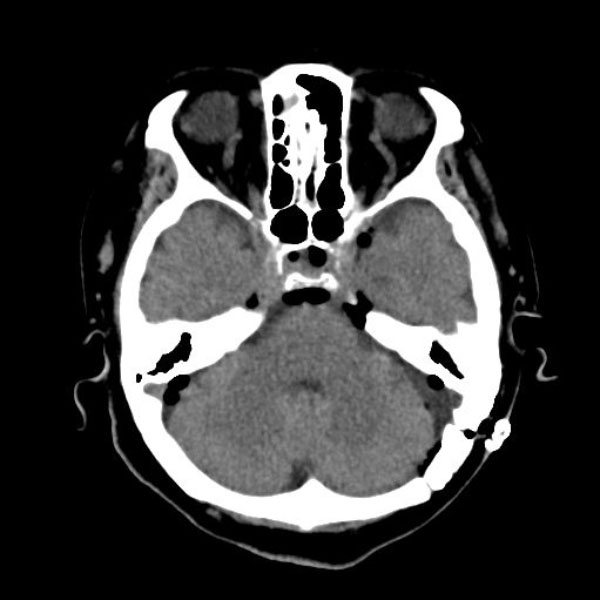

手術後

(CT)